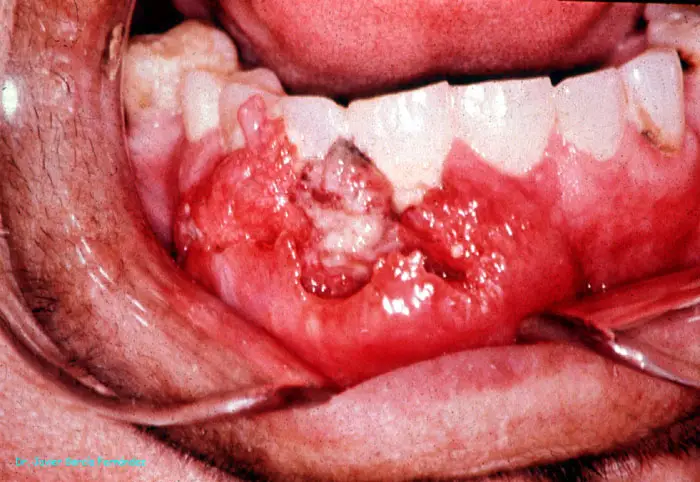

Atlas of Surgical Techniques in Periodontics. Chapter I. Diagnostic of Peridontal Diseases. Classification. Atlas de Técnicas Quirúrgicas en Periodoncia. Cap. I. Classification. Atlas de Técnicas Quirúrgicas en Periodoncia